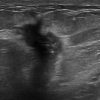

Ung thư vú

» Thông tin: Nữ giới – 55 tuổi.

» Lâm sàng: Khối tuyến vú.